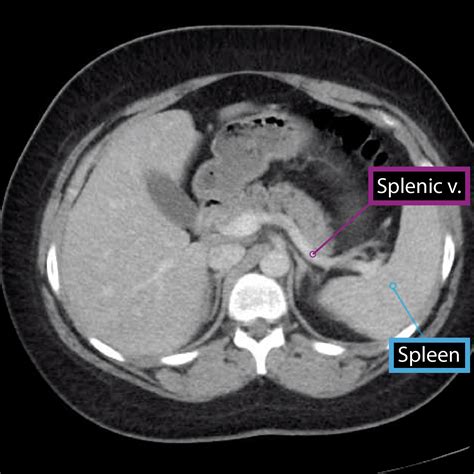

• Imaging Studies: Ultrasound, CT scan, or MRI can provide detailed images of the spleen and help diagnose conditions such as splenomegaly or splenic rupture.

• Imaging Studies: Ultrasound, CT scan, MRI, or endoscopic ultrasound can provide detailed images of the pancreas and help diagnose conditions such as pancreatic cancer or pancreatitis.

• spleen and pancreas anatomy

• spleen and pancreas location

• pancreas and splenic vein